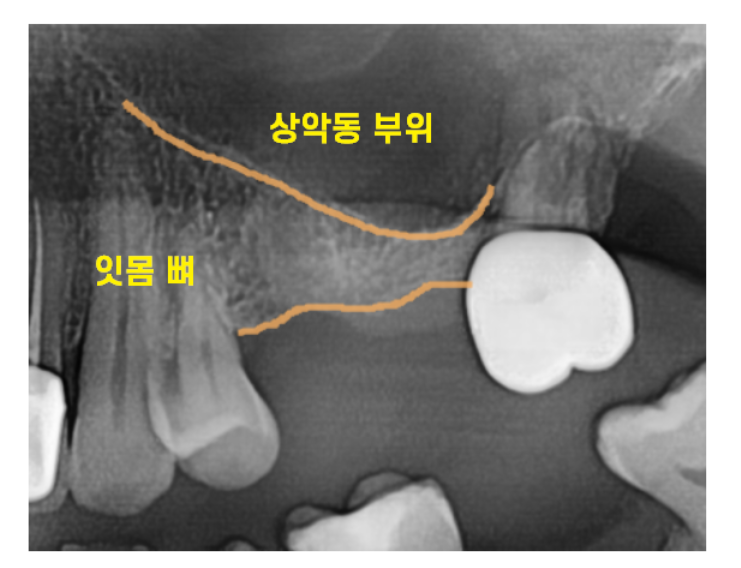

문제는 이곳이

코 안쪽 점막과 얇게 연결돼 있다는 점입니다.

상악동막이 워낙 얇기도 얇아

그 두께가 삶은 계란 먹을 때 얇은 투명한 막 정도입니다.

때문에 수술 도중 상악동 막이 뚫릴 수도 있어서

수술할 때도 집중력이 요구되는

고난이도 수술 중 하나입니다.

250711 뼈 높이가 부족하여 상악동 거상술이 필요한 경우